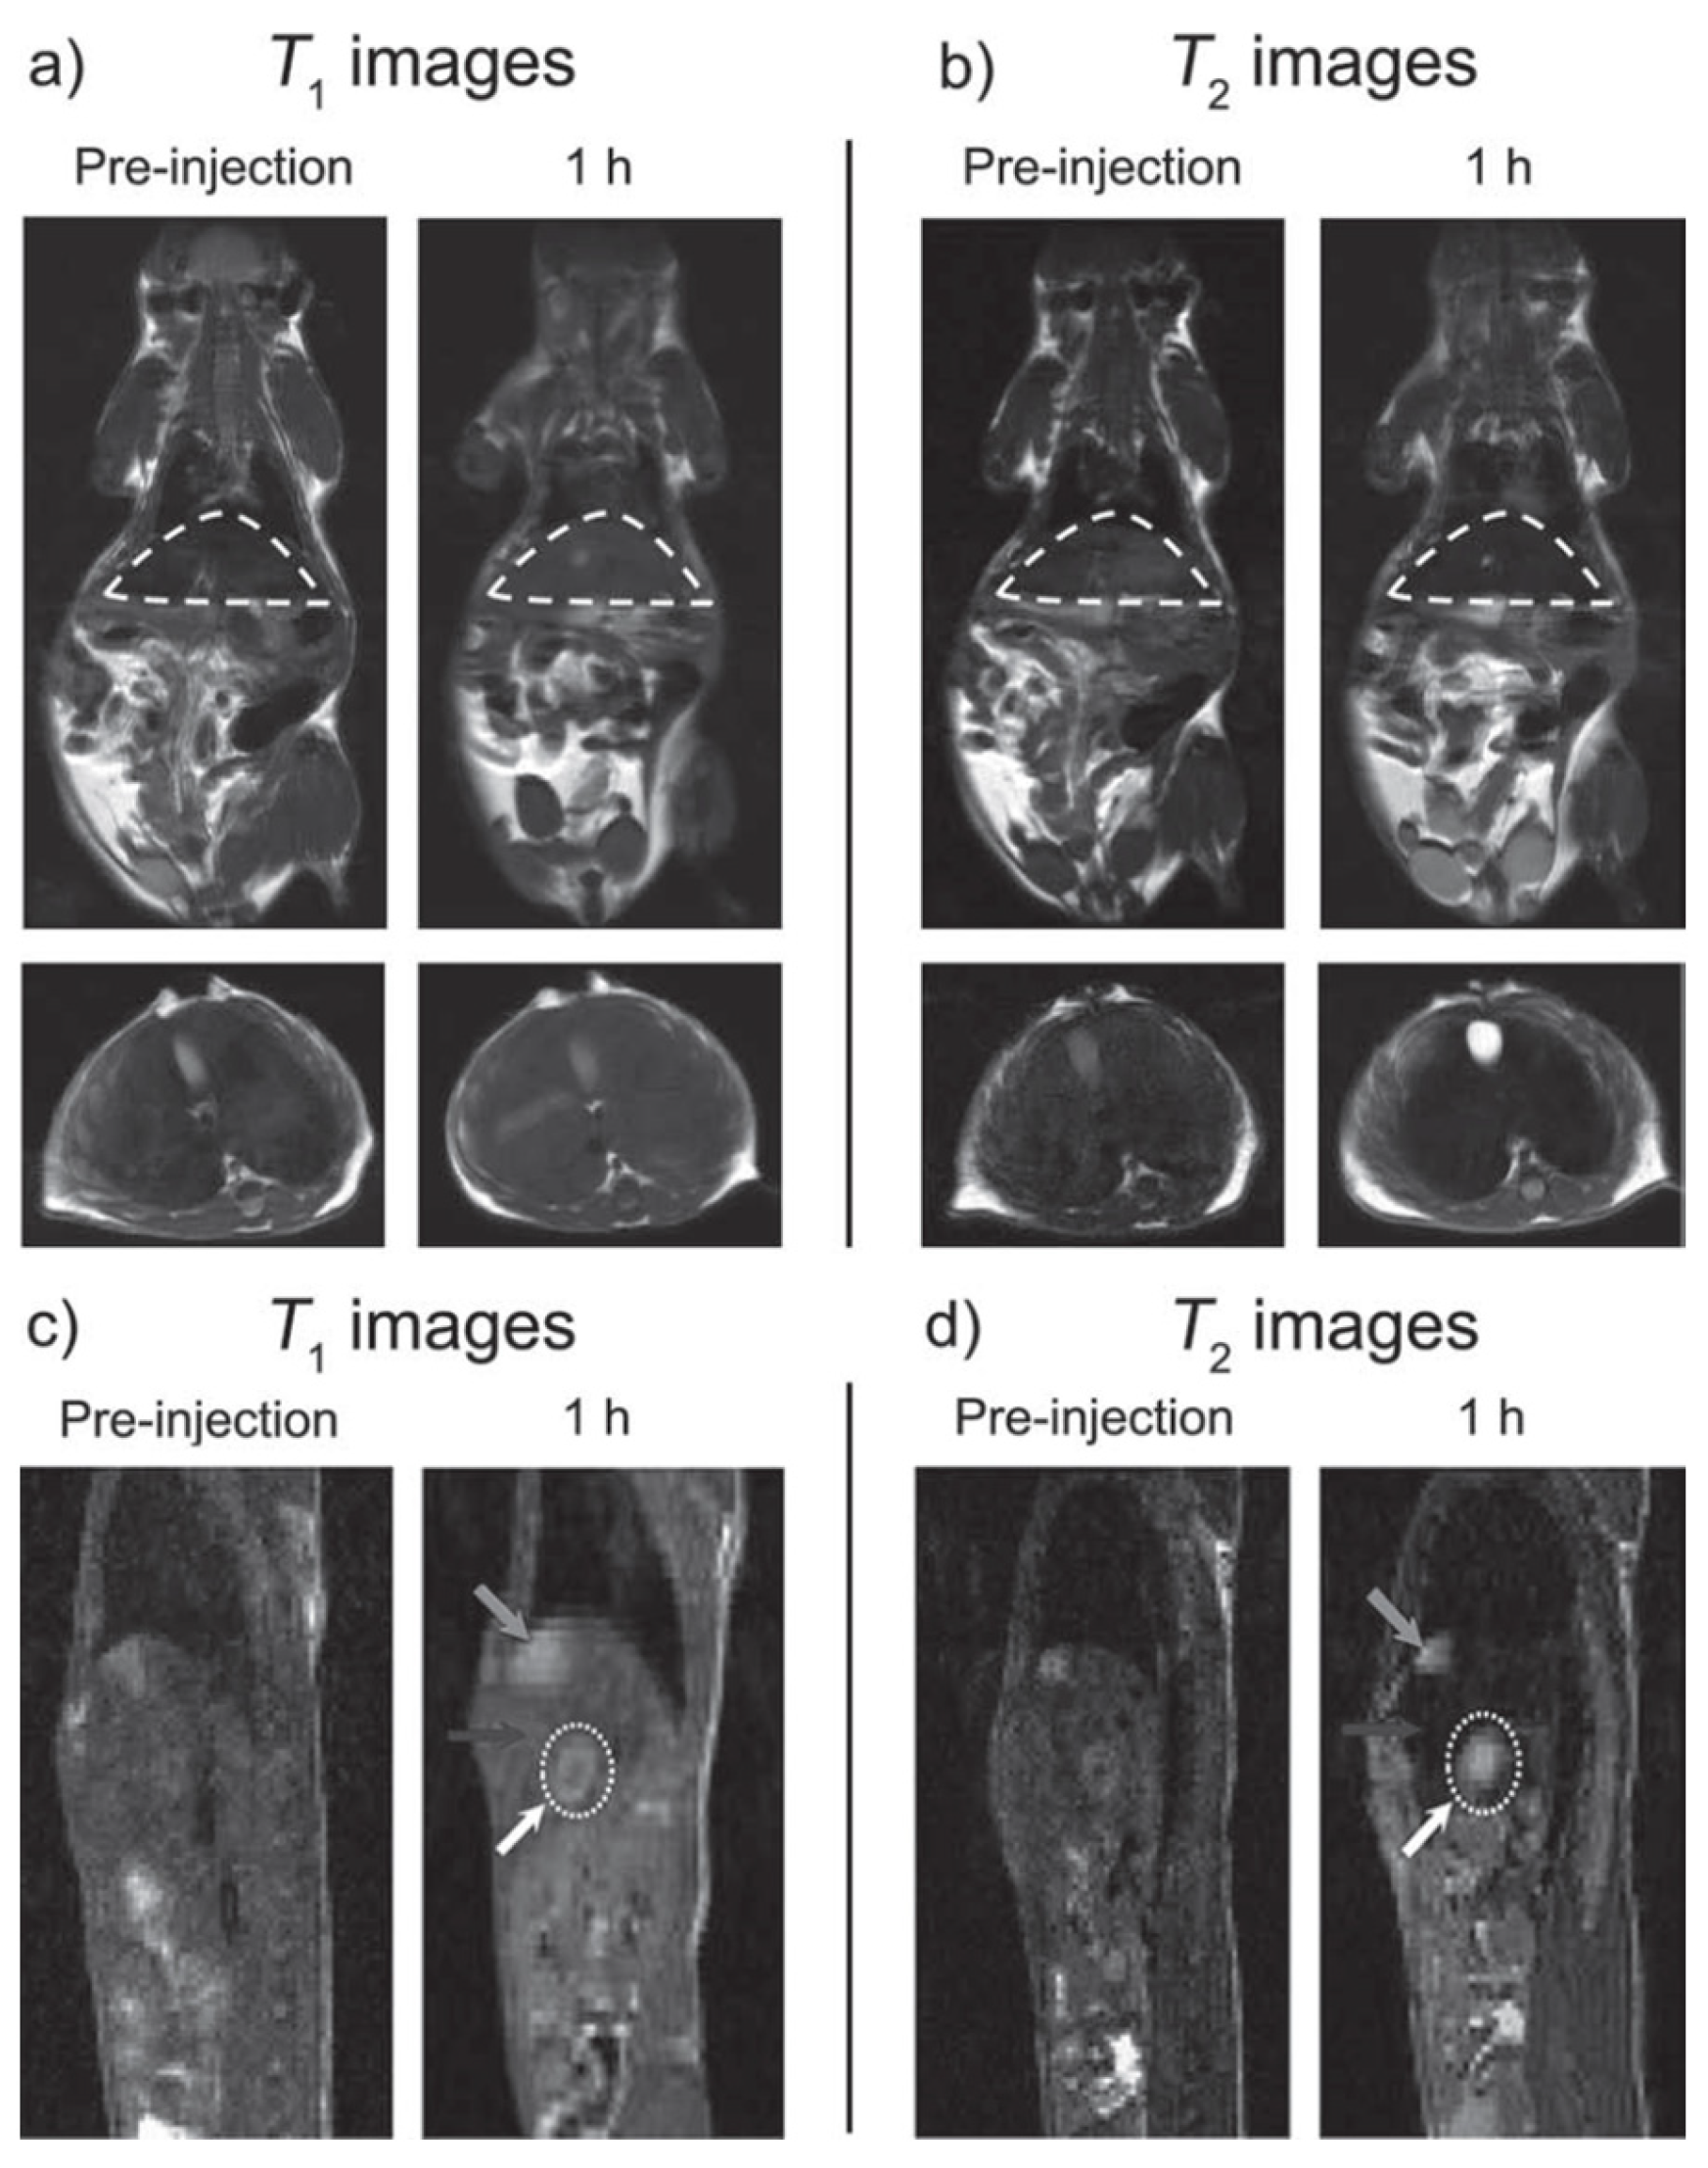

- Im, G.H.; Kim, S.M.; Lee, D.-G.; Lee, W.J.; Lee, J.H.; Lee, I.S. Fe3O4/MnO hybrid nanocrystals as a dual contrast agent for both T1- and T2-weighted liver MRI. Biomaterials 2013, 34, 2069–2076. [Google Scholar] [CrossRef] [PubMed]

| Fe3O4@MnO-PEG sphere | 1.3 | 35.8 | 28 | 3.0 | 5; - | In vitro phantoms In vivo nude mice (brain) In vivo HCC nude mouse (liver) (7 T) | [109] |

| Fe3O4/MnO-PEG dumbbell | 1.4 | 78.9 | 56 | 11; -* | |||

| Fe3O4/MnO-PEG flower | 0.6 | 141 | 235 | 21; -* | |||

| Fe3O4-PEG sphere | 0.8 | 152 | 190 | 5; -* | |||

| Fe3O4-PEG sphere | 1.1 | 162 | 147 | 11; -* | |||

| Fe3O4-PEG sphere | 1.1 | 252 | 229 | 21; -* |